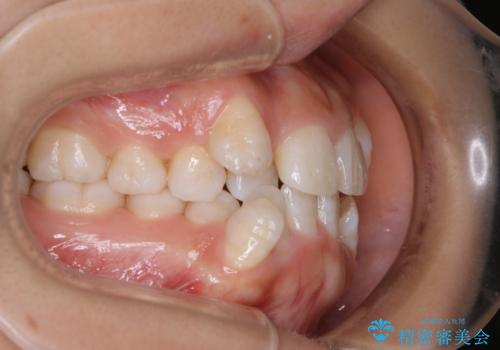

インビザライン単独での抜歯矯正治療

- 当院にてインビザライン治療を行っていた同僚の方からのご紹介でいらした方です。楽器を演奏されるとの事で、インビザラインによる矯正治療をご希望されました。治療の途中で一時的にワイヤー矯正に切り替える可能性もあることもご了承頂いた上で治療を行いました。

1日20時間以上、正しくインビザラインを使用して頂いたおかげで、ワイヤーに切り替えることなく矯正治療を終了することが出来ました。抜歯症例でしたが比較的短期間で見た目が劇的に改善し、大変喜んでいただけました。